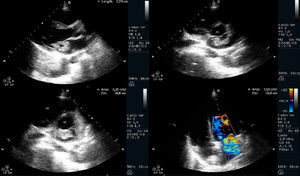

No 2.° dia de internamento, após deteção de sopro sistólico 2/6 no bordo esternal esquerdo, e em contexto de síndrome febril, foi realizado ecocardiograma transtorácico, que revelou válvula mitral com vegetação aderente à face auricular do folheto anterior, pediculada, hipermóvel, de grandes dimensões (30mm maior eixo), condicionando insuficiência mitral moderada a grave; PSAP estimada de 15mmHg (Figuras 1 e 2). Para melhor caracterização do mecanismo de insuficiência valvular e para exclusão de complicações perivalvulares, realizou ecocardiograma transesofágico, que confirmou a presença de vegetação volumosa, bem como insuficiência mitral grave, por interferência da vegetação na coaptação dos folhetos valvulares e excluiu abcesso, fístula, pseudoaneurisma ou perfuração.